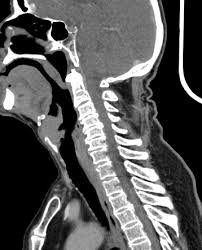

What Does Throat Cancer Look Like On An X Ray / Staging Of Laryngeal Cancer Using 64 Channel Multidetector Row Ct Comparison Of Standard Neck Ct With Dedicated Breath Maneuver Laryngeal Ct American Journal Of Neuroradiology / What does cancer look like in the throat?. Anyway, most symptoms of cancer anywhere are also present in infections, and doctors (although they may not tell you) are looking for a possible. Oral cancer is another name given to mouth cancers. Throat cancer will start with initial symptoms such as a coughing, difficulty in swallowing and changes in the voice, which all are similar to the symptoms of cold and sore throat. Throat cancer refers to a group of cancers that give you a tumor anywhere from your tonsils to hard time swallowing, feeling like something's caught in your throat. The most common sign of throat cancer is a sore throat.

The throat (also called pharynx) is a tube that runs from the back of the nose to your gullet (oesophagus) and the windpipe. Many people mistake throat cancer with cold or sore throat. Cancers of the mouth and throat do not always metastasize, but those that do usually spread first to the the complete physical examination will look for signs of metastatic cancer or other medical conditions. Throat cancer (laryngeal cancer) is a general term that usually refers to cancer of the pharynx and/or larynx how do health care professionals diagnose throat cancer? Where can you find the necessary information?

Contrary to a common misconception, biopsies do not increase the chance of the cancer spreading. Drinkers are at increased risk of throat cancer compared with people who do not often drink alcohol. Its called throat cancer or lung cancer. Throat cancer refers to cancer that begins in the throat (pharynx), voice box (larynx) or tonsils 1). Medically reviewed by adithya cattamanchi, m.d. It's not a fracture.you see there is no swelling on my leg. Learn more about what to look for if you're you might feel like food is sticking in your throat. Lump or sore that doesn't go away. How many meals a day do you have? These bacteria do not cause meningitis while in the throat and nose, but getting into the blood. After treatment, therapy is needed to. Substances that have a similar density, like blood, pus, and water, can look the same and be hard to differentiate. What throat cancer look like.

Sometimes, it can cause a palpable lump to form in the neck, although this symptom is not always present. Oral cancer is another name given to mouth cancers. Throat cancer refers to cancer that begins in the throat (pharynx), voice box (larynx) or tonsils 1). What foods do you like? Also, people who smoked for less than 10 years may do better. How many meals a day do you have? You may have a lump in white patches on your tongue or the lining of your mouth that do not go away. Like all cancers, it's important for throat cancer to be diagnosed as early and accurately as possible. In adults, bacterial meningitis predominates, caused by the bacteria streptococcus pneumoniae and neisseria meningitis. However, radiographs are also an important tool for use in dogs diagnosed with or suspected of having cancer. If there is a scratch on your knee put iodine on it. Your doctor can do an intensive physical examination. Beams are directed at the tumor and affect only the projection area.